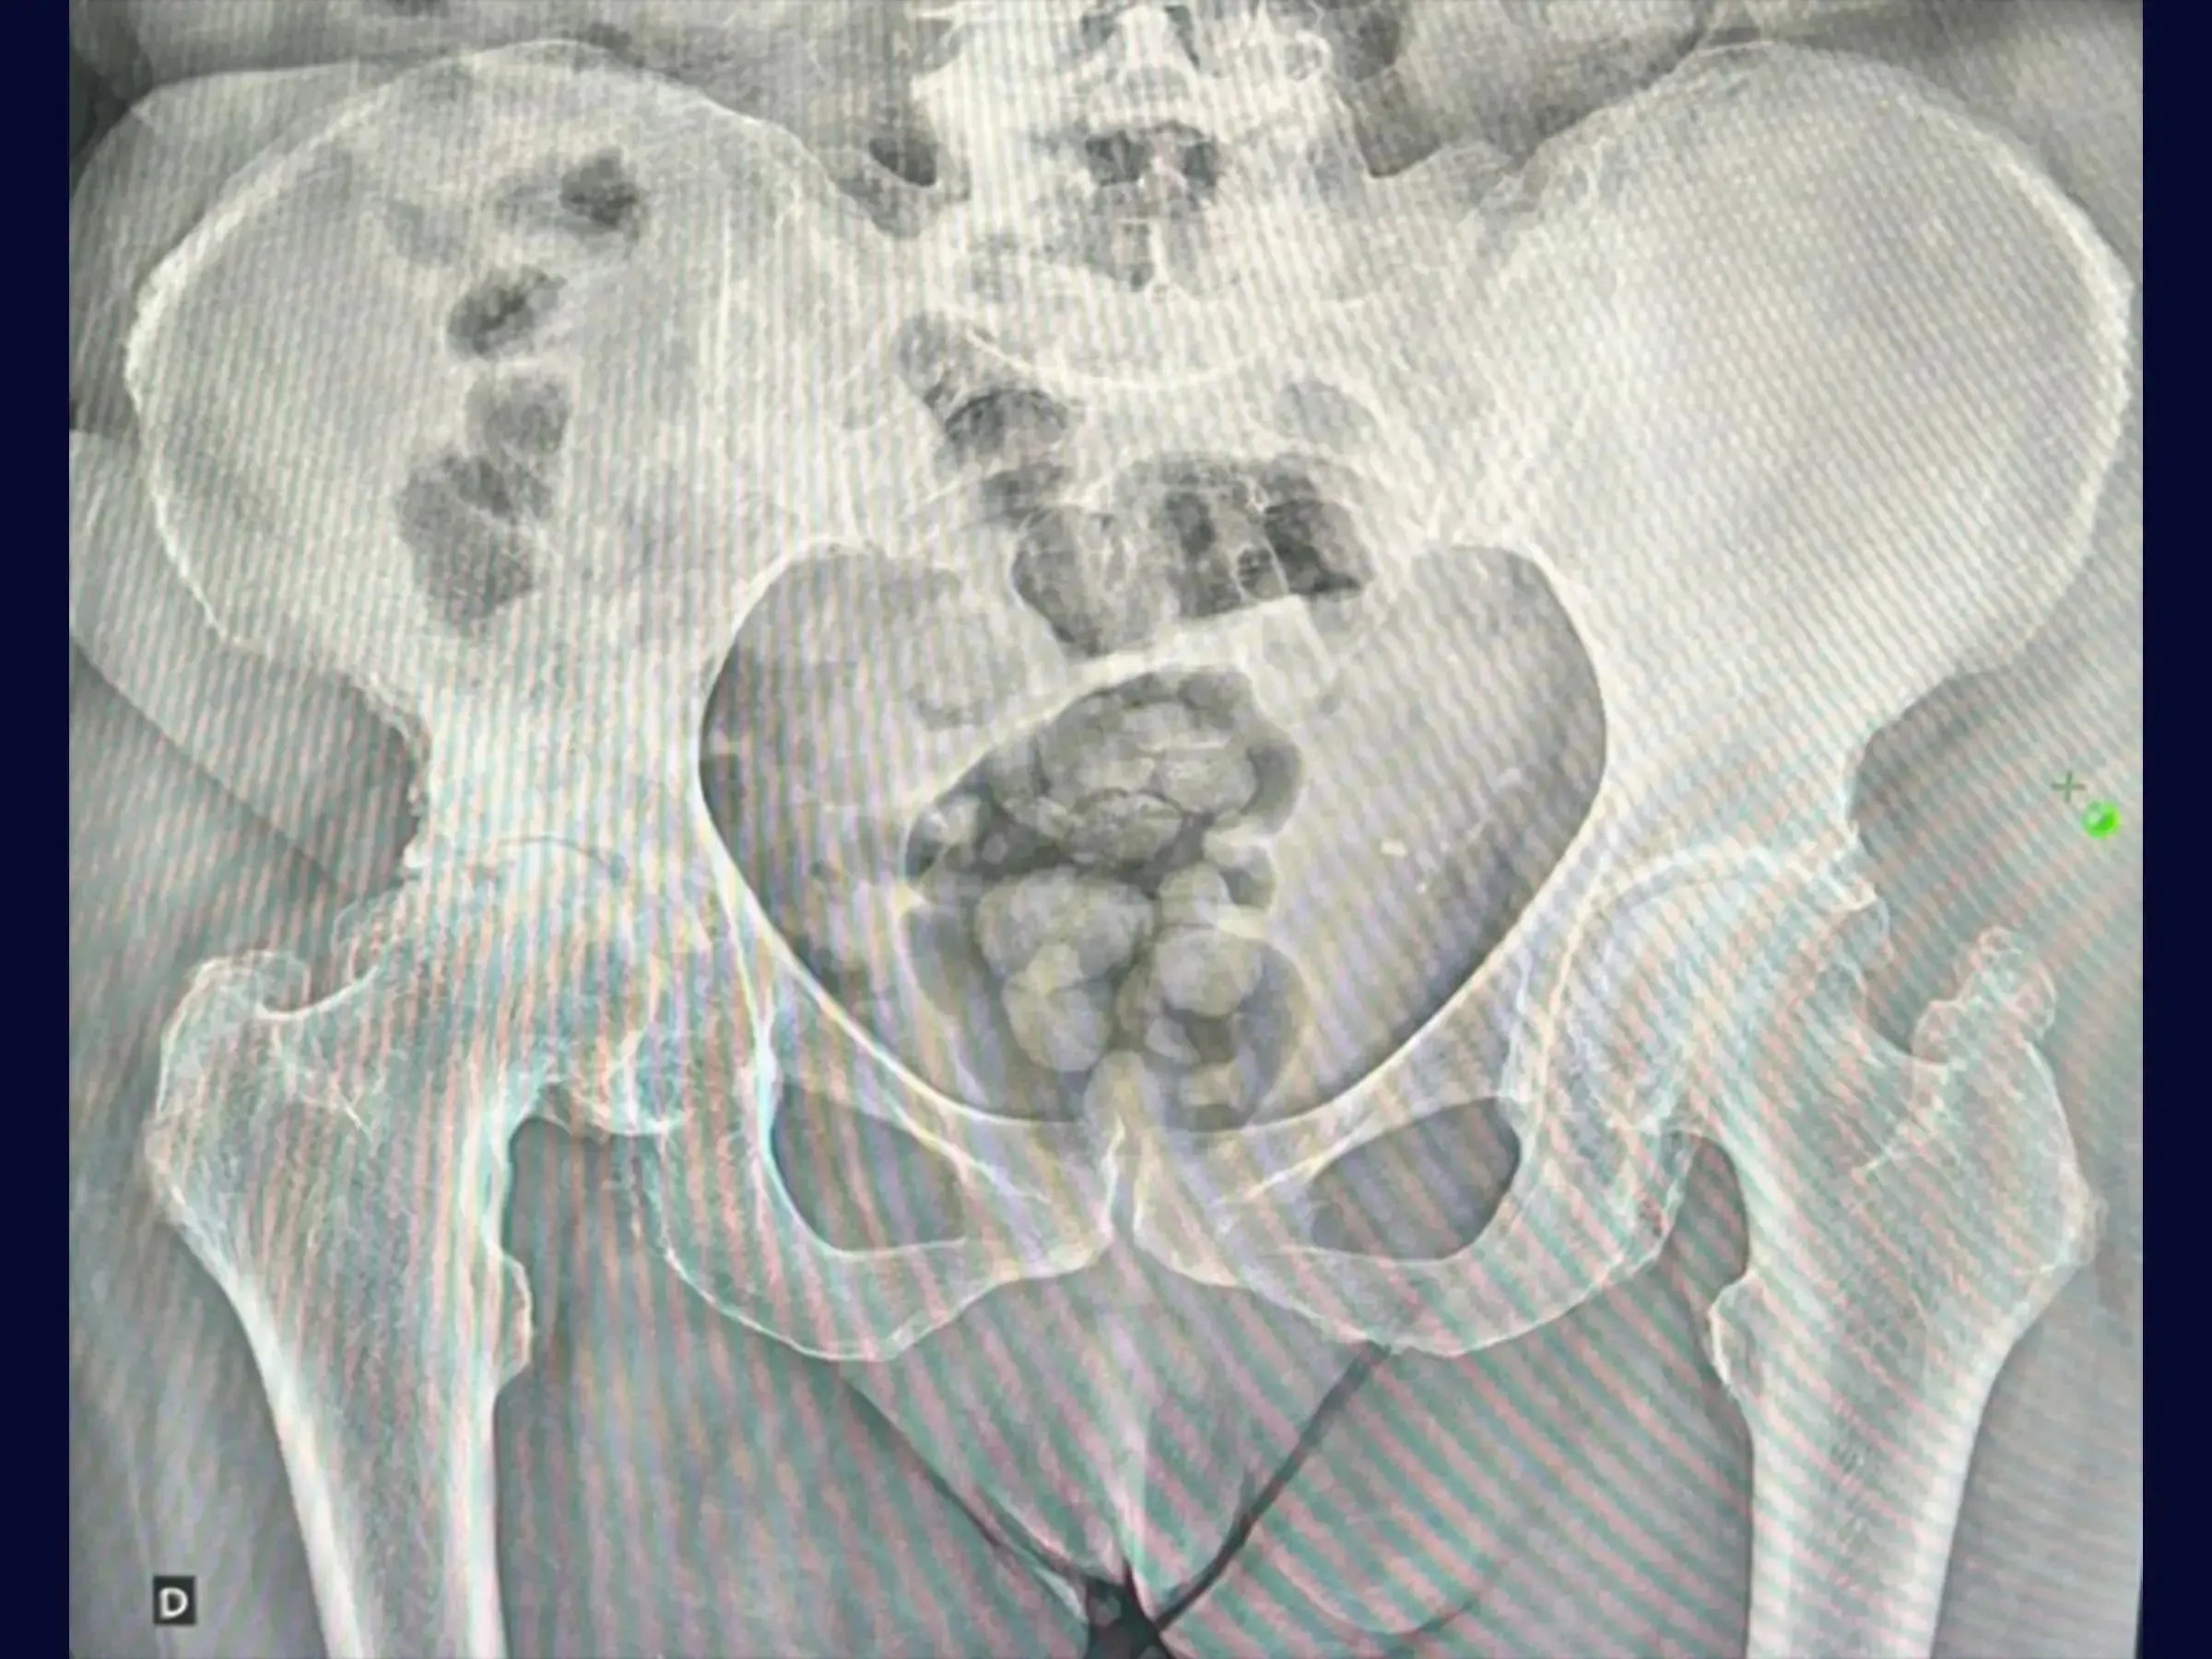

- Preparación Acetabular Optimizada: Protocolos de limpieza completa del labrum y tejidos blandos, exposición del hueso subcondral y una técnica de fresado que inicia en el fondo del acetábulo para evitar la “cadera alta”, asegurando el molde para el implante.

- Fresado Acetabular con Control de Ángulo: Estrategias para establecer el ángulo correcto, proteger el techo y la región posterior y fresado continuo para uniformidad y prevenir la forma ovalada.